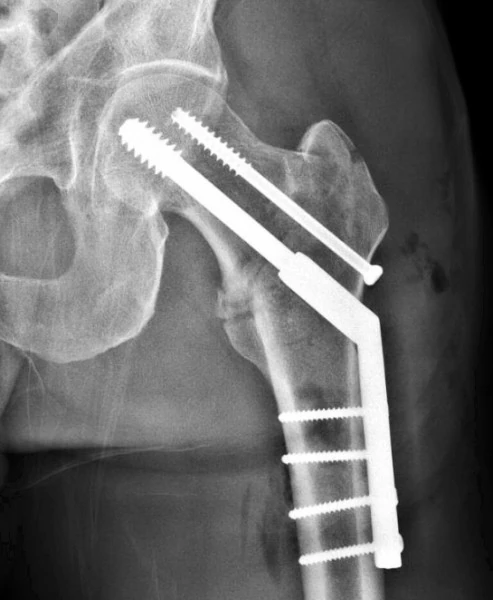

So, I had nearly 30 miles by the time the car was fixed. I drove the car back to Vincent’s in Arvada and got over 60 mpg, so the battery helped a ton. Then Vincent spent a half hour trying to open the x-ray. It takes special software, which I don’t understand. Eventually Vincent got the 3 images to open. It didn’t look so good to me. My hip seemed to be pretty healed, but there is a knob at the top of the hip that seemed to of moved. I remembered asking my doctor in Iowa about that a month ago and he said that they don’t mess with that and it would heal itself.

So I was stressed and sent off a few pictures to my Iowa guy, Matt, and Stacie from Louisville. I didn’t hear back for a little while, so Vincent and I rode over to Golden to spin. Eventually Matt texted me back and said what he had said before, that he wouldn’t fix it and that I’m going to limp around for a while longer because of it. My hip has hurt a lot recently. Like enough I can’t sleep again. That is why I got the x-ray to start with. I guess I’m glad it isn’t something worse, but am bummed that the knob, (officially tip of the greater trochanter) moved over. I guess it’s never going to be in the right place. Seems like there should be some bone glue to just stick it back into place.

Anyway, it is what it is. I’m broken still. I guess I’ll just keep doing what I’m doing. The doctor said that my hip abductors insert in that area, but “the bone is NO way structural or compromises the integrity or repair of the hip”. That is good. It doesn’t help with the sleep, or walking, or riding, but it is good.